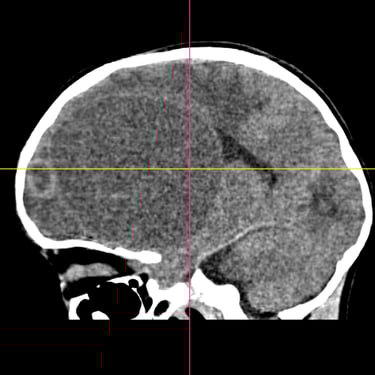

El absceso cerebral es una infección localizada del parénquima cerebral que produce acumulación de pus e inflamación, generando cefalea, fiebre, alteración del estado de conciencia o déficit neurológico focal. El diagnóstico temprano es fundamental para evitar complicaciones graves. La tomografía cerebral con contraste es el estudio de elección inicial, ya que permite visualizar una lesión hipodensa con realce en anillo característico. Posteriormente, la resonancia magnética complementa la evaluación. El tratamiento combina antibioticoterapia dirigida y, en casos seleccionados, drenaje quirúrgico o resección. La detección oportuna mediante imágenes mejora significativamente el pronóstico del paciente.